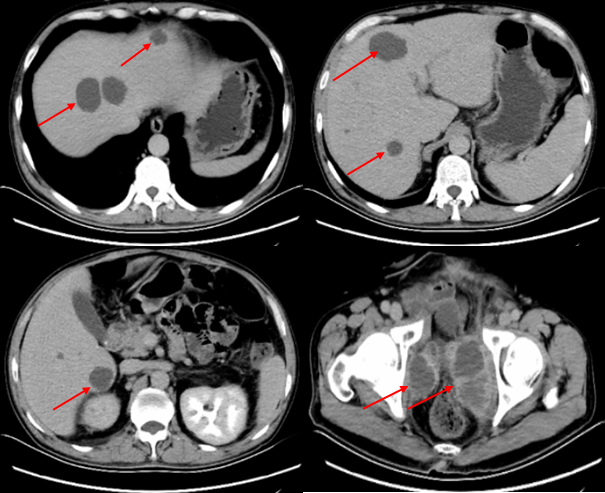

患者一般情况较差,考虑患者盆腔多发转移,建议尽早行免疫治疗,在沟通疗效和价格等因素后,患者自行选择信迪利单抗。2019年1月7日,给予信迪利单抗单药(200mg,ivgtt)治疗一周期,同时继续评估转移情况。2019年1月25日进一步完善全腹部增强CT示肝脏及盆腔内多发转移瘤(图3)。

图3 患者肝脏及盆腔多发转移瘤(2019年1月25日)

2019年3月1日复查全腹部CT增强扫描示:肝及盆腔内多发转移瘤。对比2019.1.25前片,肝内部分病灶及盆腔病灶缩小(图4)。

患者2019年1月25日(发现盆腔多发转移病灶后1个月)检查发现肝脏出现多发转移性肿瘤,考虑患者病情进展迅速且疾病负荷较大,而免疫治疗起效相对较晚,调整治疗方案为信迪利单抗免疫治疗联合白蛋白紫杉醇化疗。治疗期间定期复查,肝脏转移灶和盆腔病灶明显缩小及消失,疗效PR。截至2019年9月,患者共接受白蛋白紫杉醇(100mg)qw化疗23次,末次化疗时间2019年8月,信迪利单抗(200mg)q3w治疗13次,末次治疗时间2019年9月18日,一线治疗PFS为9个月。